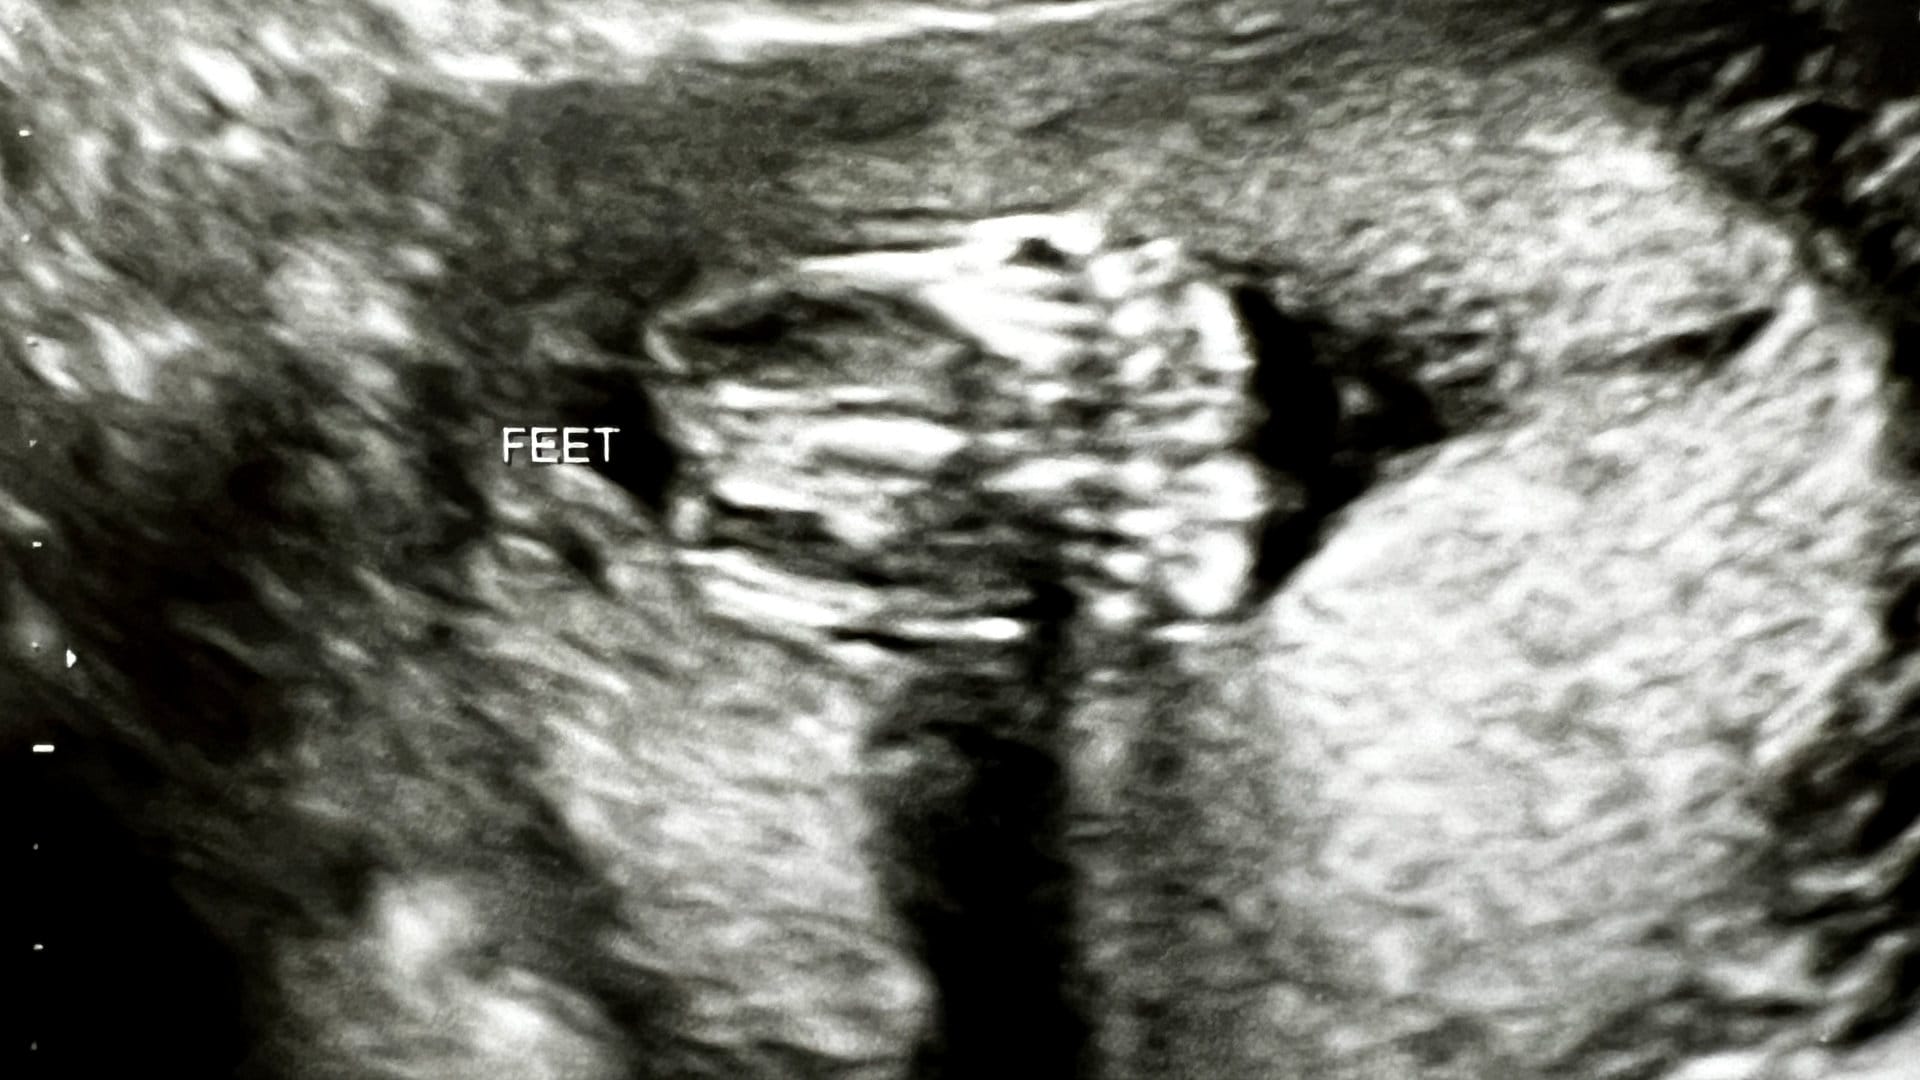

During the past five years, I've been in the OR for three brutal C-sections, the first of which was an emergency job due to infection that landed us a five day hospital stay while my wife's white blood cell count came down from the stratosphere.

I've stood and watched two C-sections as the OB pressed and pushed on my wife's abdomen with the ferocity of CPR after a car crash and watched the doc unwrap the umbilical cord from around my son's neck like an instant replay of a rodeo in reverse.

Three times I've heard that life-changing freeze-frame amniotic-fluid-filled gasping first cry that's simultaneously louder than a sonic boom and softer than a whisper.

I've walked with my wife through the month long and then some recovery process from getting a six inch abdominal incision. It's a major surgery with major surgery recovery timelines.